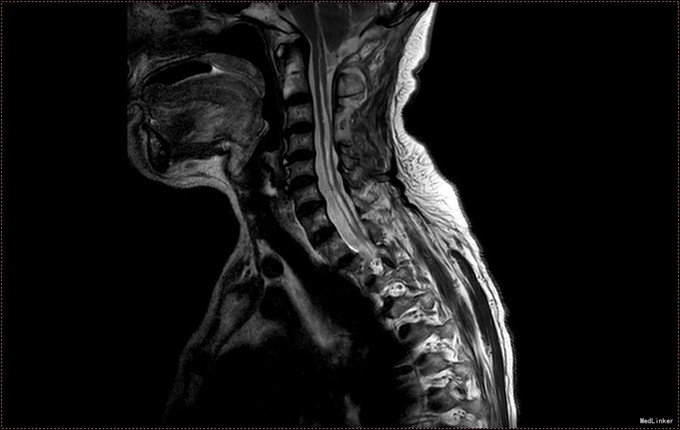

入院查体:神清语明,问答准确,查体合作,精神状态良好。双侧瞳孔等大正圆,D≈3.0mm,双侧眼球活动自如,对光反射灵敏。双下肢肌力减退,肌力三级,肌张力正常。双上肢肌力正常,活动自如。四肢感觉减退,可见多处烫伤瘢痕。双巴氏征(-)。 颈椎MR提示小脑扁桃体下疝畸形,脊髓空洞症(C1-T6);颈椎管狭窄,颈椎间盘膨出(C3-C6)

患者诊断明确,完善术前检查。行枕下减压,扩大修补硬膜,颈髓空洞穿刺。术后予常规治疗。复查颈椎MR提示小脑扁桃体减压充分,脊髓空洞略缓解。但术后3日起发热,行腰穿提示椎管内感染,行腰池引流1周,拔管出院。出院时患者自述左侧肢体麻木感减轻,双下肢肌力较入院好转。